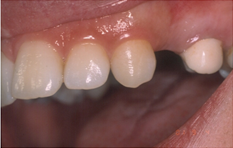

Απουσία του άνω πρώτου προγόμφιου